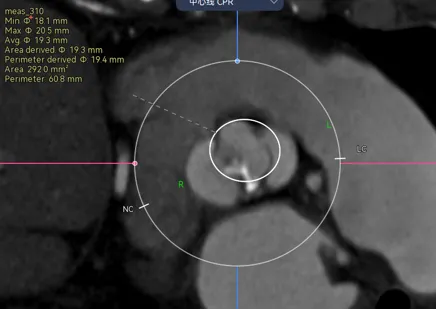

病例3 - 瓣上6-9mm的地方偏前交界缘的地方有一块钙化,如果是没有经验的可以能会这么画。

那就错了,需要先评估钙化重不重,对瓣膜有没有可能推挤,这里有个小诀窍,一般在瓣叶中间的钙化是可以推开的,除非他连接了基底部,而在交界区的钙化往往对瓣膜推挤作用和很强,做预估时要避开钙化的限制,如下图

结合下图术后CT可以看到,我对瓣膜位置的预判基本正确,钙化与升主的限制共同把瓣膜推向小弯侧,这时候可以看到瓣膜距离冠脉开口非常之近,如果再贴近一点,瓣膜植入再高一点,裙边或者吊桥可能会有冠脉阻挡风险。所以像这种单边钙化的冠脉风险也是需要看看的。